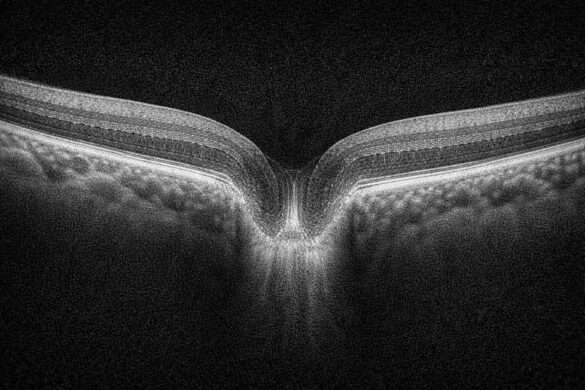

実はこれ、「視神経乳頭の周囲をぐるっと一周スキャンした断面」を帯状に引き伸ばして表示している画像なんです。

この円周上をスキャンして得られたAスキャン(断層情報)を連続的につなぎ合わせることで、ぐるっと一周分の断面図=Bスキャン画像が作られます。

このBスキャン画像、じつは円形の断面を引き延ばしたものなので、普通の断面とはまったく形が違います。

上下に波打ったような形や、左端と右端がつながっているように見えるのは、視神経の周囲を一周した結果を“平面”に並べているからです。

- 断層像の上に見えるのがRNFLの厚み(上側の盛り上がり)

- RNFLが薄いところは「谷」のように見える

- 時計回りでの位置関係を意識して、どこに変化があるかを確認します